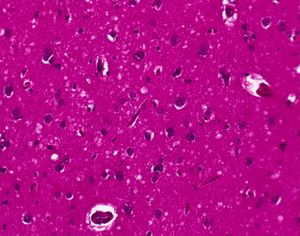

| Tonsil biopsy in variant CJD. Prion Protein immunostaining. | |